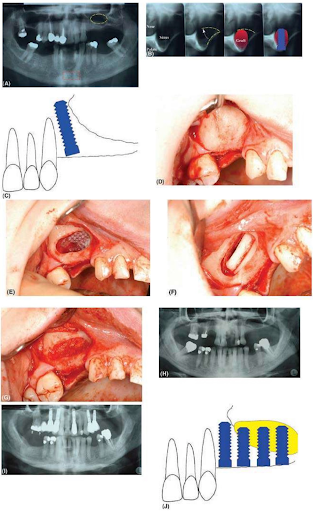

(A) Phim toàn cảnh của một bệnh nhân cần đặt implant ở hàm trên sau. Sống hàm có chiều cao tốt nhưng phần kéo dài của xoang hàm trên ở phía bên trái làm cho ta không thể đặt nhiều hơn một implant mà không ghép. Không có dấu hiệu của bệnh lý viêm xoang hoặc mức chất lỏng/niêm mạc dày lên. Ngoài ra, không có vách xương trên vách phía bên. Vùng đề xuất cho mô ghép xương từ cằm cũng được vạch ra. (B) Hình ảnh cắt lớp của bệnh nhân được hiển thị trong phần A cho phép đánh giá khoảng trống có sẵn để nâng cửa sập xương (thể hiện bằng đường màu vàng) Một biểu thị thể tích miếng ghép cần thiết có thể được xác định cũng như độ dài của implant có thể được đặt. Lượng xương còn lại trong trường hợp này không đủ để ổn định implant ở giai đoạn nâng xoang. Implant sẽ được đặt sau đó ba tháng. (C) Bệnh nhân trong phần A có thể được đặt một implant vào vùng xương phía xa răng cối nhỏ trên bên trái . Điều này có thể đủ ở những bệnh nhân đường cười thấp hoặc chịu lực thấp nhưng điều trị này hiếm khi được chọn trừ khi thay thế răng cối nhỏ thứ hai trên. (D) Hình ảnh trước phẫu thuật thành bên của xoang. Ở đây thành xoang dày và không có dấu hiệu của xoang, thường thể hiện bằng một màu xanh xuất hiện nơi có xương mỏng nhất. (E) Cửa sổ được tạo ra với một mũi khoan acrylic (acrylic bur) và màng xoang đã được nâng lên. Màng đã không còn nguyên vẹn và lỗ thủng được bảo vệ bằng một màng tự tiêu. Chiều cao xương còn lại không đủ 5mm để cho phép vừa nâng xoang vừa đặt implant, do đó miếng ghép sẽ được đặt vào khoảng trống vừa tạo ra. (F) Khoảng trống còn lại trong hốc được nhét xương tự thân, ở phiến xương được lấy từ cành đứng xương hàm dưới. (G) Vật liệu xương khác bao gồm hỗn hợp vụn xương được đặt xung quanh miếng ghép và các cạnh ngoài của khoảng trống. Miếng ghép có thể được che phủ bởi một màng tự tiêu ở mặt ngoài để chắc chắn miếng ghép nằm trong khoảng trống. Sau đó vạt được khâu lại. (H) X quang trước phẫu thuật cho thấy chiều cao hạn chế của xương hàm trên phía sau. (I) X quang sau phẫu thuật sau khi nâng xoang ở hàm trên bên trái. Có thể nhìn thấy tương quan giữa độ cao mới của sàn xoang với các implant. Xương còn lại ở hàm trên bên phải còn đủ nên có thể đặt implant mà không cần ghép. (J) Ghép khối xương lớn có thể được giữ vững bằng cách đặt implant xuyên qua cả xương và miếng ghép. Lý tưởng nhất là miếng ghép nên được định hướng để các phiến xương vỏ ở phía trên cho phép cố định tốt chóp của implant.

Mũi khoan tiến tới việc di chuyển màng khi lớp xương bên ngoài bị lấy đi và nền xoang được đẩy lên qua đường cửa sổ.

Mức độ mà sàn xoang được nâng lên cũng được quyết định bởi vị trí của lỗ tự nhiên (lỗ osteon) trên vách ngăn mũi, cái mà cho phép xoang dẫn lưu. Một khi khoảng trống được tạo ra trong xoang thì có hai cách khác nhau để đặt implant. Nếu xương ổ răng còn lại có đủ chiều cao và cố định được implant (thường ít nhất là 5mm chiều cao) thì ta có thể được đặt ngay lập tức, khoảng trống còn lại lấp đầy bằng vật liệu ghép. Nếu khối xương lớn được đặt vào xoang, ta có thể cố định bằng cách đặt các implant xuyên qua cả mô ghép và xương ổ răng. Trong trường hợp xương ổ răng còn lại rất ít, khoảng trống trong xoang được ghép trước và đặt implant sau ba tháng. Kỹ thuật này có lẽ là lựa chọn được ưa thích với tiên lượng tốt hơn trong mọi trường hợp. Vật liệu ghép ưa thích là xương tự thân, mặc dù xương này thường được trộn với vật liệu khác ghép khác. Nên cẩn thận khi sử dụng vật liệu hạt ghép để đảm bảo rằng màng xoang còn nguyên vẹn hoặc bất cứ chỗ rách nào cũng được bịt kín và được bảo vệ. Một khi vật liệu ghép và / hoặc implant được đặt vào, các cửa sập xương, nếu có, được giữ ở vị trí trên cao, việc khâu đóng các vết thương sẽ đơn giản. Quyết định đặt một màng GBR bên ngoài cửa sổ tùy thuộc phẫu thuật viên, một số bằng chứng cho thấy nếu có màng thì việc ghép thành công hơn.